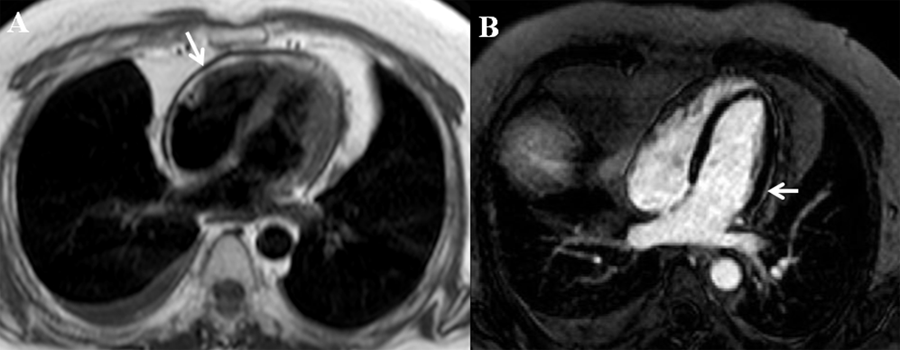

In our patient, idiopathic transient constrictive pericarditis (CP) was diagnosed. Due to persistent symptoms on medical therapy and poor performance on CPX, the patient underwent pericardiectomy with improved symptoms. On CMR, axial black blood image showed up to 5 mm circumferential pericardial thickening (Figure A arrow) and delayed enhancement imaging with phase sensitive inversion recovery showed very mild lateral pericardial gadolinium enhancement (Figure B arrow), suggestive of minimal residual inflammation. Pericardial inflammation and edema can lead to pericardial thickening resulting in poor compliance of the pericardium and eventually constrictive physiology. With conventional medical therapy the use of triple anti-inflammatory therapy with nonsteroidal anti-inflammatory drug, colchicine and steroids delayed enhancement and constrictive physiology can be reversed.1,2 Transient CP was first described in 1987 by Sagristà-Sauleda et al where 9% of patients identified with effusive acute idiopathic CP had reversible constriction after a mean period of 2.7 months.3 Immuno-modulating agents, such as azathioprine and the interleukin-1 receptor antagonist (anakinra), can be considered in refractory recurrent cases or when use of steroid sparing agents is preferred. However, use of these agents in CP are not standardized and further prospective randomized trials are needed.4-6 In our patient, there is only minimal residual inflammation on CMR and he had failed multiple trials of conventional medical therapy, therefore early referral for pericardiectomy should be considered.

Figure A: Cardiac magnetic resonance imaging in the setting of constrictive pericarditis showing pericardial thickening (arrow) on axial black blood image.

Figure B: Mild pericardial enhancement (arrow) suggesting residual pericardial inflammation is seen on delayed enhancement imaging with phase sensitive inversion recovery on cardiac magnetic resonance imaging.